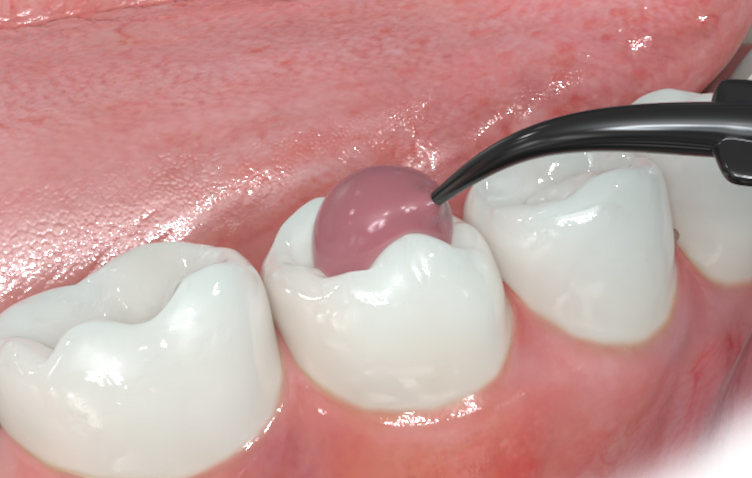

Halt für Kofferdam-Klammern

Nutzen Sie J-Temp als Halt für Kofferdam-Klammern und als Barriere für endodontische Spüllösungen.